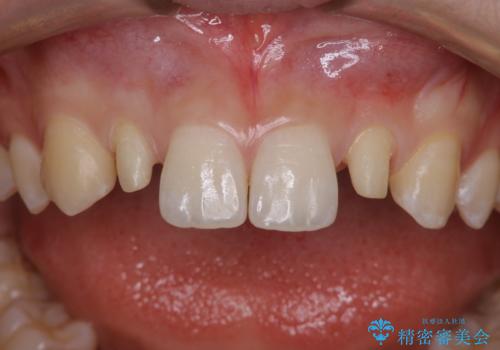

- 初診時、前歯部の見た目の改善を主訴にご来院されました。生まれつき歯が小さい状態の「矮小歯」とそれに伴う正中の「すきっ歯」があるため、大きなガタつきはないものの笑った時の印象に違和感が出る状態となっていました。

矮小歯が傾斜していることなどを踏まえ、より安全に治療を進めるために部分矯正を併用したセラミッククラウンでの治療を行うこととなりました。

前歯や小臼歯では、生えてくる歯が小さく審美的に影響が出る場合があります。このような歯を矮小歯(わいしょうし)と言います。

今回のケースでは、歯が小さいだけでなく傾斜もしていたため補綴治療時に歯を削ることで神経の症状が出る可能性がありました。そのため、事前に部分矯正を行い歯軸の改善を行っておくことで、歯髄を温存することができました。